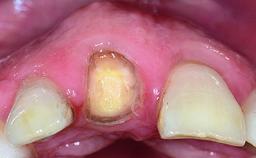

A healthy 37-year-old female patient was referred for a consultation on the replacement of missing tooth 21 with an implant-supported restoration. She stated that several years previously the tooth had been traumatically avulsed following a motor vehicle accident. The tooth was replaced with a three-unit fixed partial denture (FPD) immediately afterwards. Over time, she became disillusioned with the FPD and looked for a different option, including orthodontic therapy. She presented still in her orthodontic appliances, with the pontic sectioned free from the FPD but attached to the archwire. Her orthodontist felt that orthodontic treatment had been successfully completed, but nevertheless referred her before removing the appliances in case adjustments were necessary.

Bone Volume Deficient horizontally, allowing simultaneous augumentation